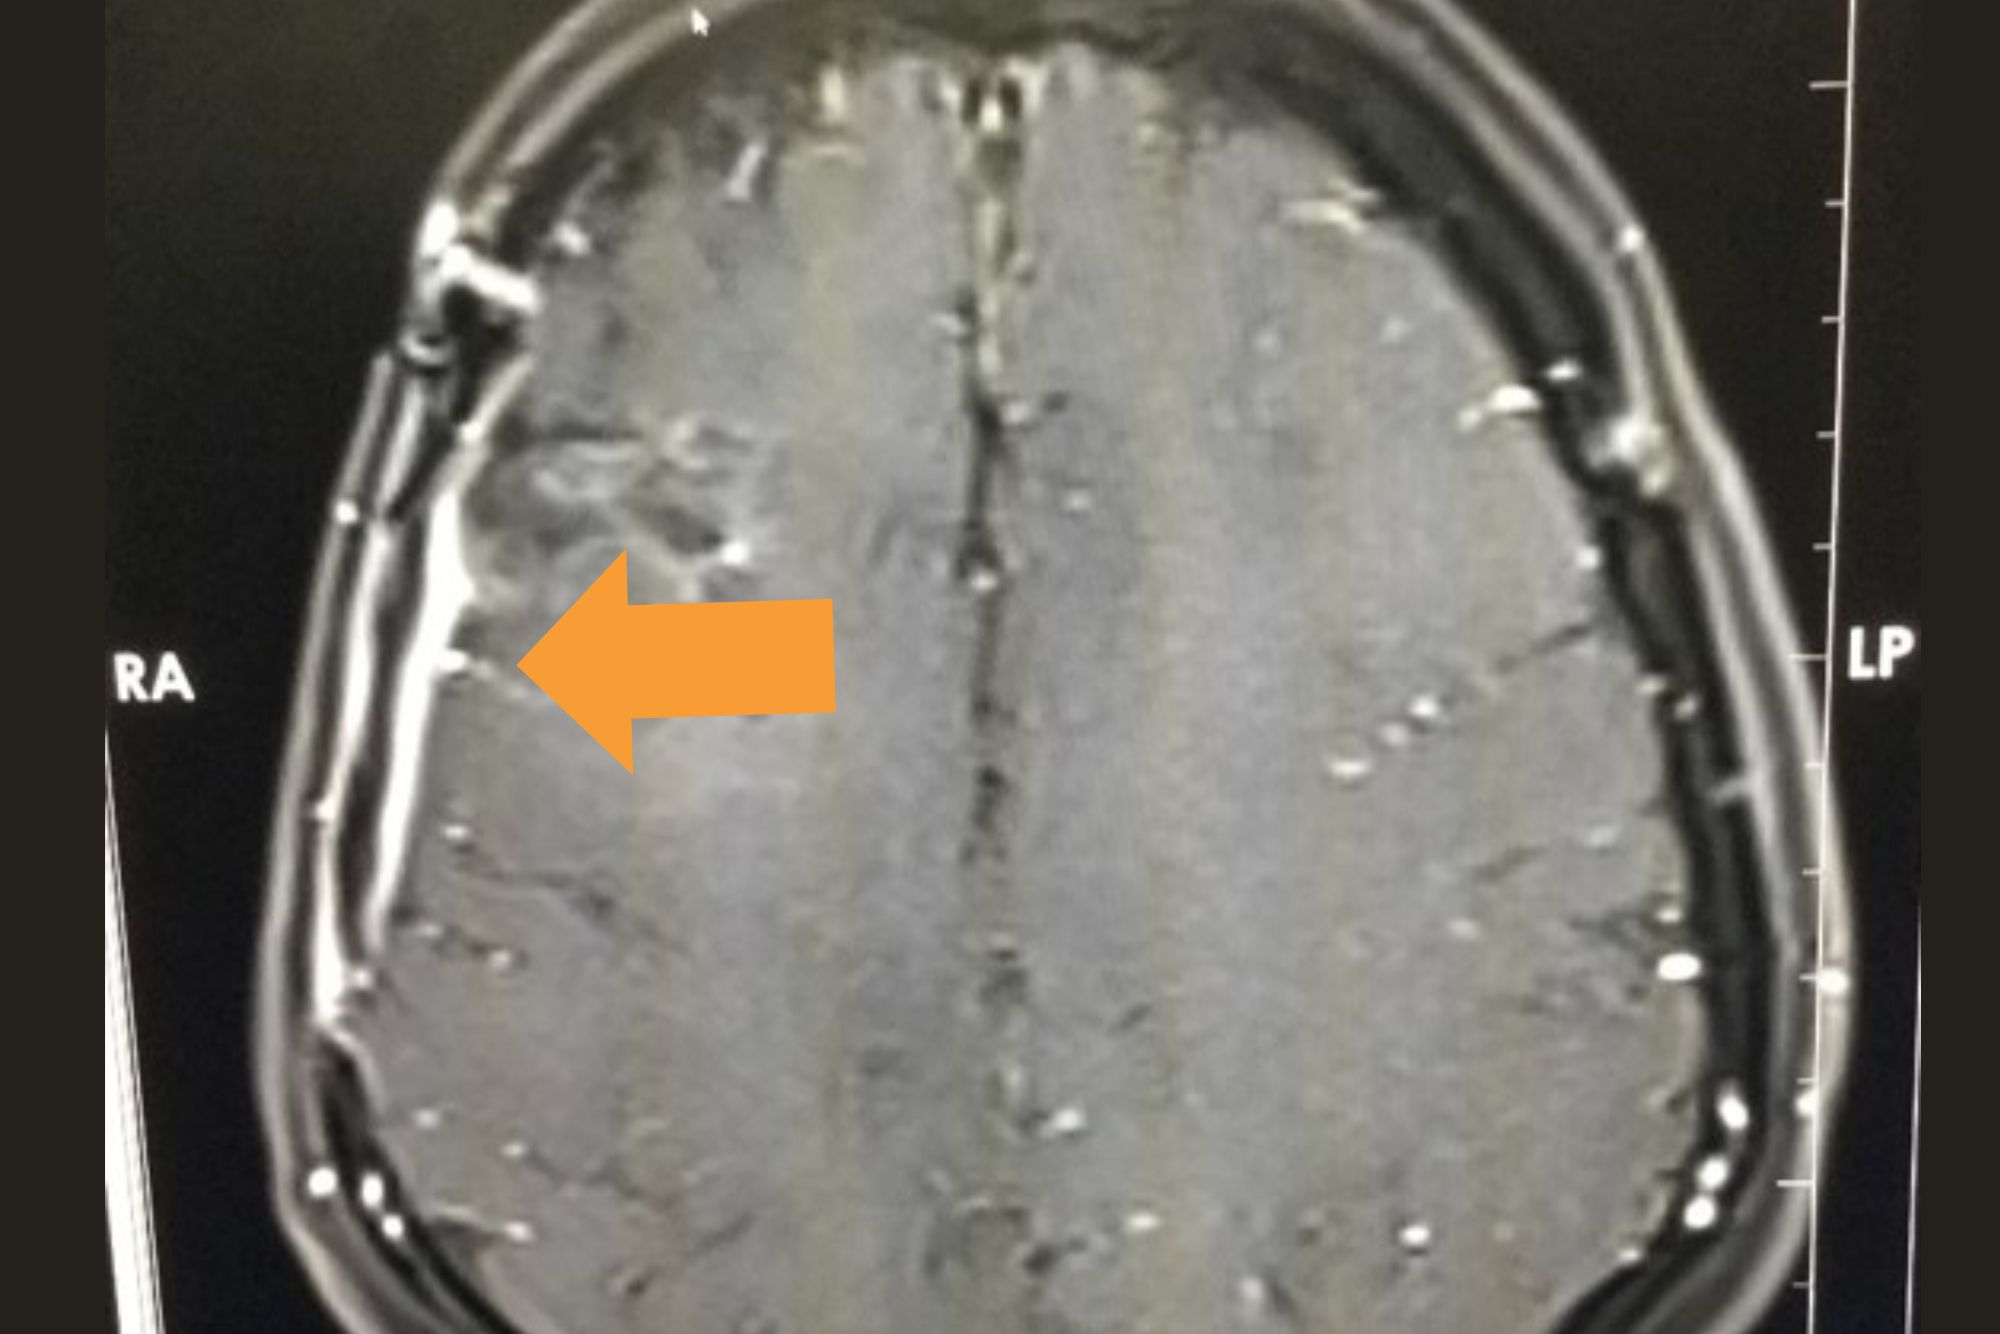

1 year Post operative contrast MRI

Cavernoma

Preoperative MRI